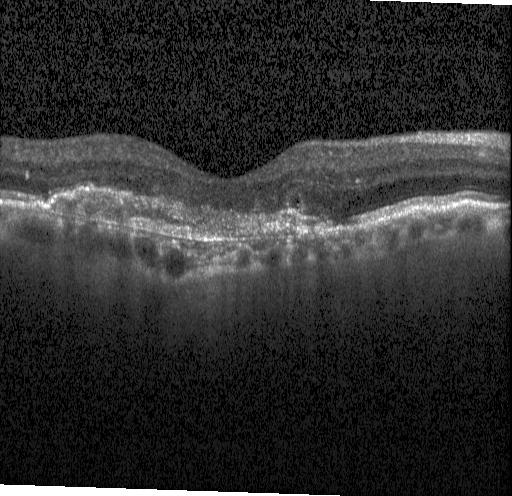

Dataset: Retinal OCT · 4 classes

Retinal OCT

4-class retinal OCT classification: CNV, DME, Drusen, Normal